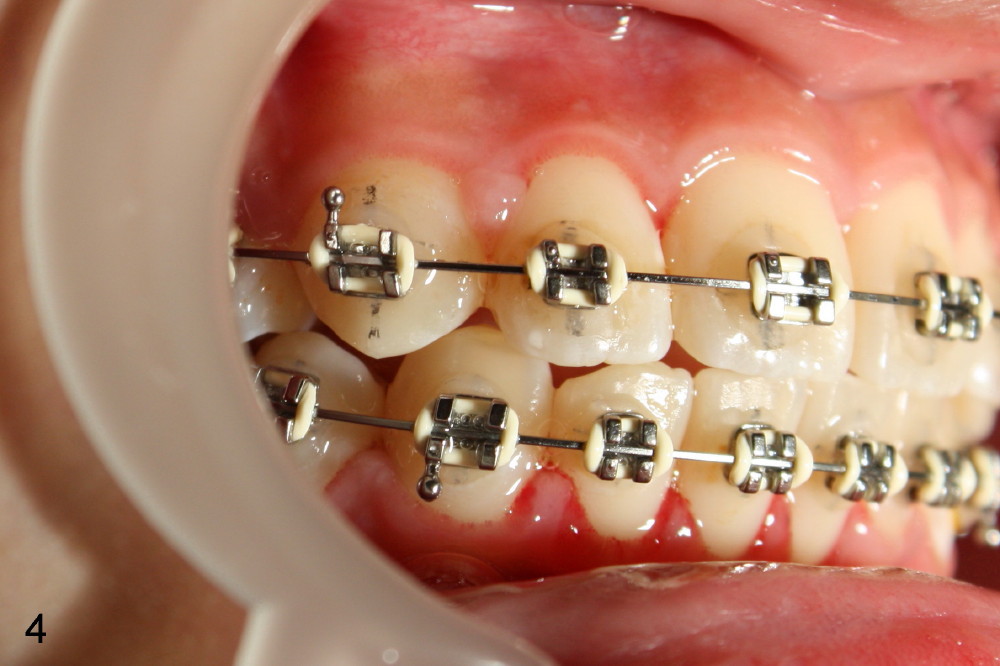

Rebracketing at #6 (Fig.3) leads to resolution of the anterior open bite within a month (Fig.4).